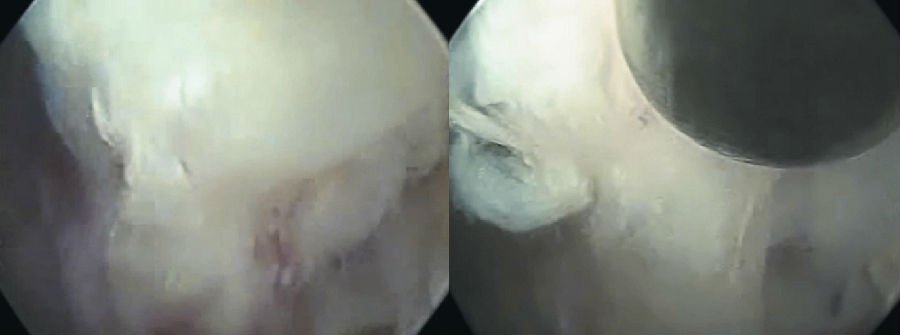

8. 镜下操作

采用一次性双极射频手术刀头、Punch钳、小直钳、磨钻依次切除或修整部分肥厚或钙化的黄韧带、椎体后缘增生的骨赘、椎体后缘对神经根造成压迫的外层纤维环及其边缘的硬化或骨化结构、与后纵韧带粘连的增生结缔组织,对神经根背侧和腹侧进行全面的减压松解,特别是神经根下方的微小硬化性组织。(图16~图21)

图16 内镜下显示套管内视野中间纤维环

图17-图20 内镜下显示套管内视野中间纤维环;内镜下小直钳取髓核;取出部分髓核后张力下降,神经张力间接下降;转动工作套管显露硬膜囊和周围组织

9. 双极射频使破裂的纤维环消融皱缩成形。观察可见硬膜囊自主搏动,神经根表面血运明显改善,血管充盈,神经根复位,术中行直腿抬高试验,可见神经根被牵拉后滑移自如。(图22、图23)

10. 旋转工作套筒检查视野内无出血、残余碎片等,确认无异常后移除内镜及工作套管。切口缝合1~2针。(图24)

图21-图24 取出的髓核组织(中间部分硬化);下行根头端减压;硬膜囊、下行根减压后神经松解,博动良好;手术切口(大小约8mm)